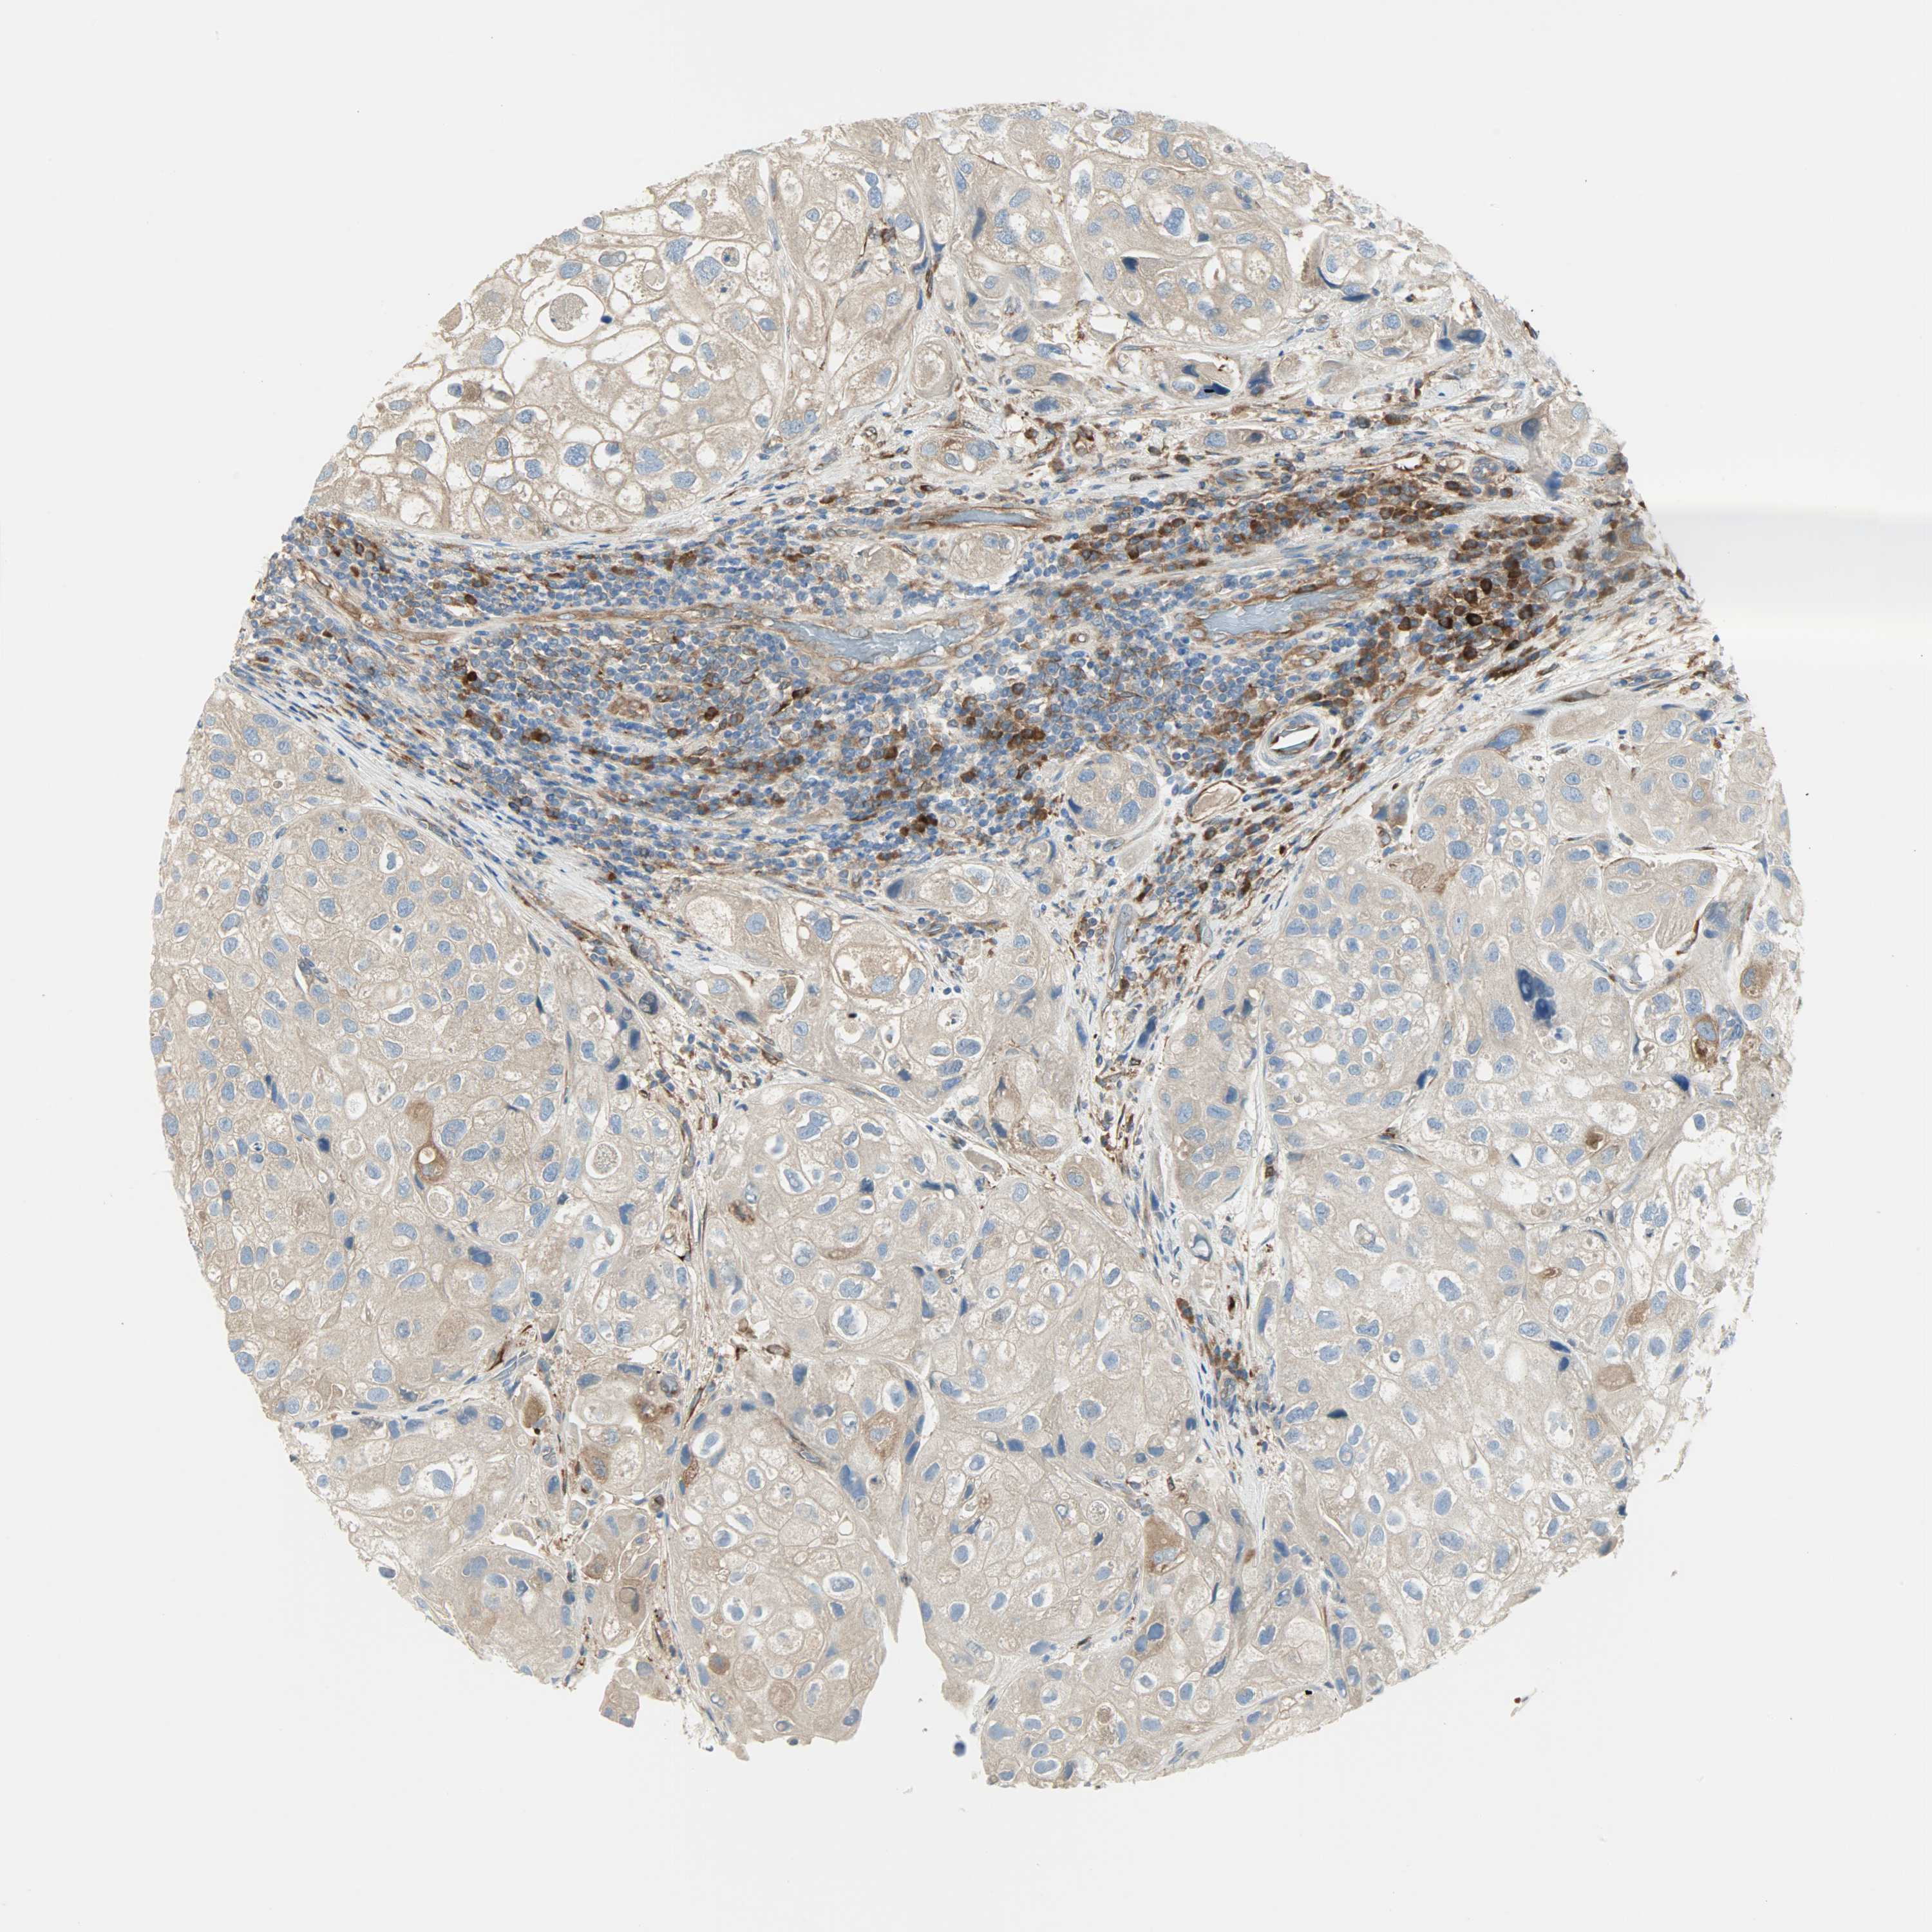

UROTHELIAL CANCER - Protein expressioni

A mouse-over function shows sample information and annotation data. Click on an image to view it in a full screen mode. Samples can be filtered based on level of antibody staining by selecting one or several of the following categories: high, medium, low and not detected. The assay and annotation is described here.

Note that samples used for immunohistochemistry by the Human Protein Atlas do not correspond to samples in the TCGA dataset.

Antibody stainingi

Antibody staining in the annotated cell types in the current human tissue is reported as not detected, low, medium, or high, based on conventional immunohistochemistry profiling in selected tissues. This score is based on the combination of the staining intensity and fraction of stained cells.

Each image is clickable and will lead to virtual microscopy that enables deeper exploration of all samples and also displays staining intensity scores, fraction scores and subcellular localization as well as patient and tissue information for each sample.

Antibody HPA005573

Staining

High

Medium

Low

Not detected

Intensity

Strong

Moderate

Weak

Negative

Quantity

>75%

75%-25%

<25%

None

Location

Nuclear

Cytoplasmic/membranous

Cytoplasmic/membranous,nuclear

Urothelial carcinoma, High grade

Urothelial carcinoma, Low grade